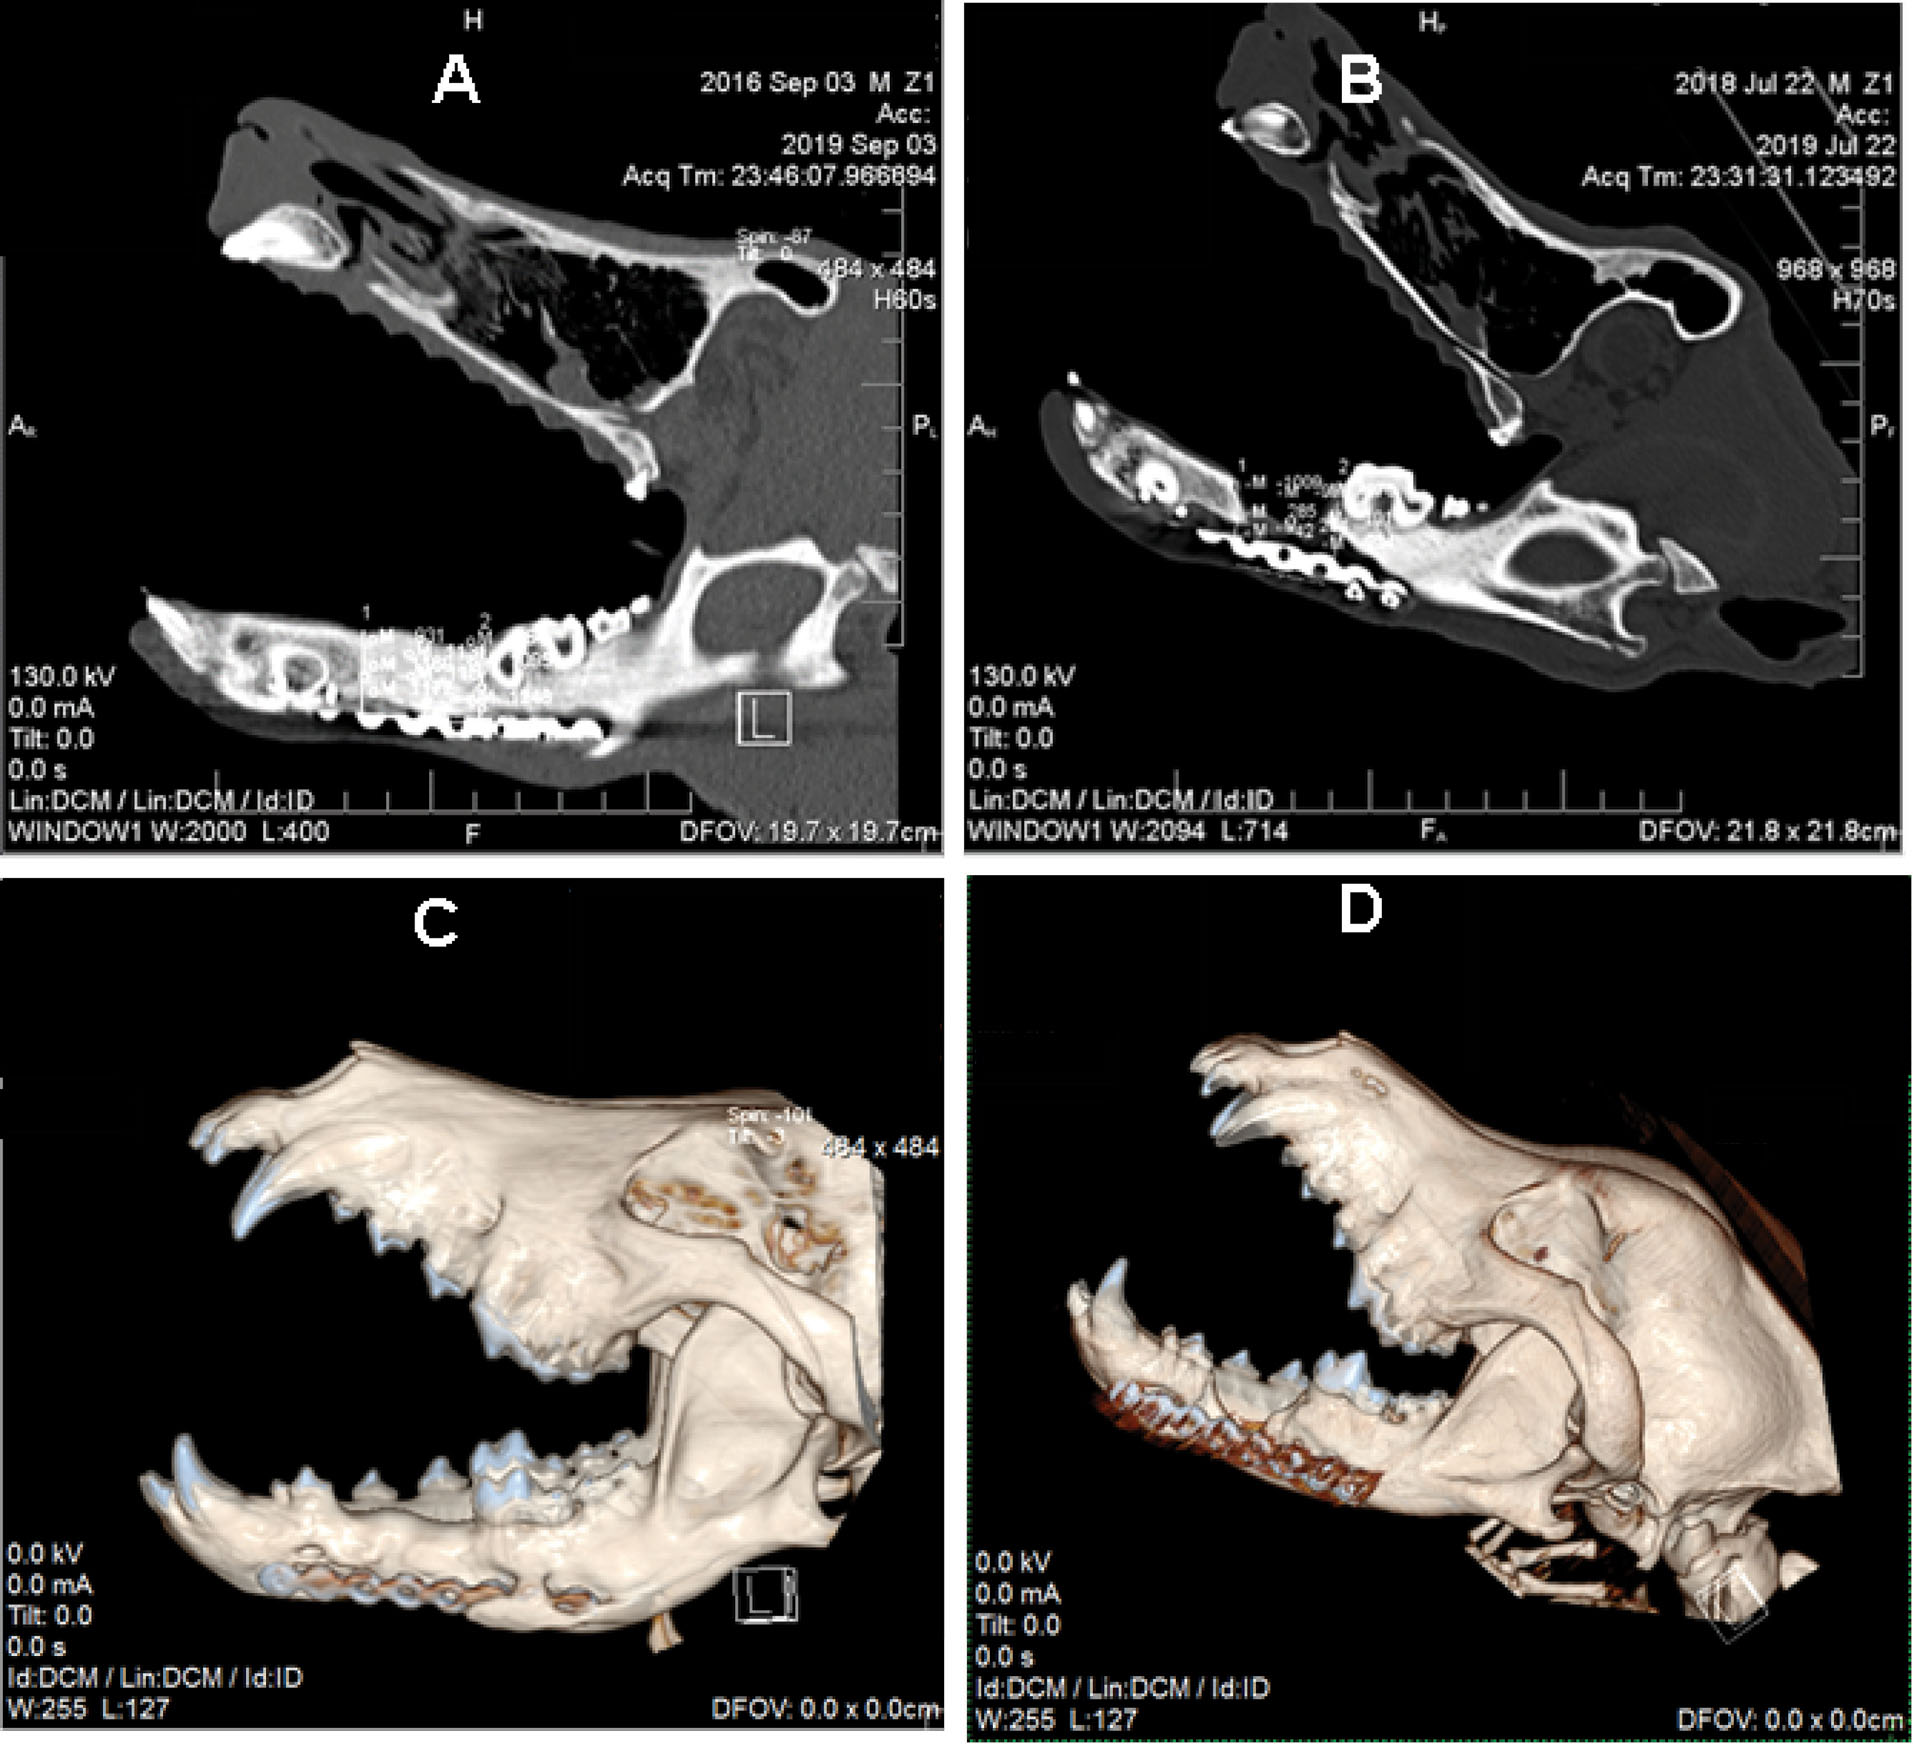

After six months, the samples were examined through a CT scan at the defect site for bone regeneration rate evaluation. One dog in the ASCs group was excluded from the study because of infection. The comparison of bone density with HU showed that it was -123.6 ± 32.1 HU in the control group and 511 ± 5.1 HU in the ASCs group (). According to the t-test, a significant difference (P< 0.001) was observed in the bone density of these two groups. illustrates CT scan images of mandibular canines in the treatment and control groups. Bone formation is evident in the treated group compared to the control group (). In the 3D construction of the CT image, the ASCs group exhibited a significantly higher bone density than the control group ().

Figure 5.

Figure 6.

CT scan images of canine mandible. (A) Sagittal section of the ASCs group. (B) Sagittal section of control group. (C) 3D reconstruction of canine skull of the ASCs group. (D) 3D reconstruction of canine skull of the control group.